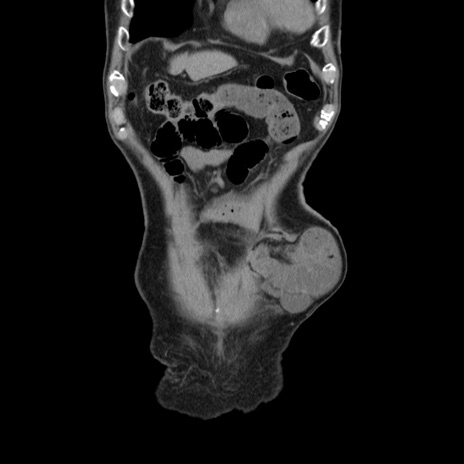

症例24(冠状断像)

横断像